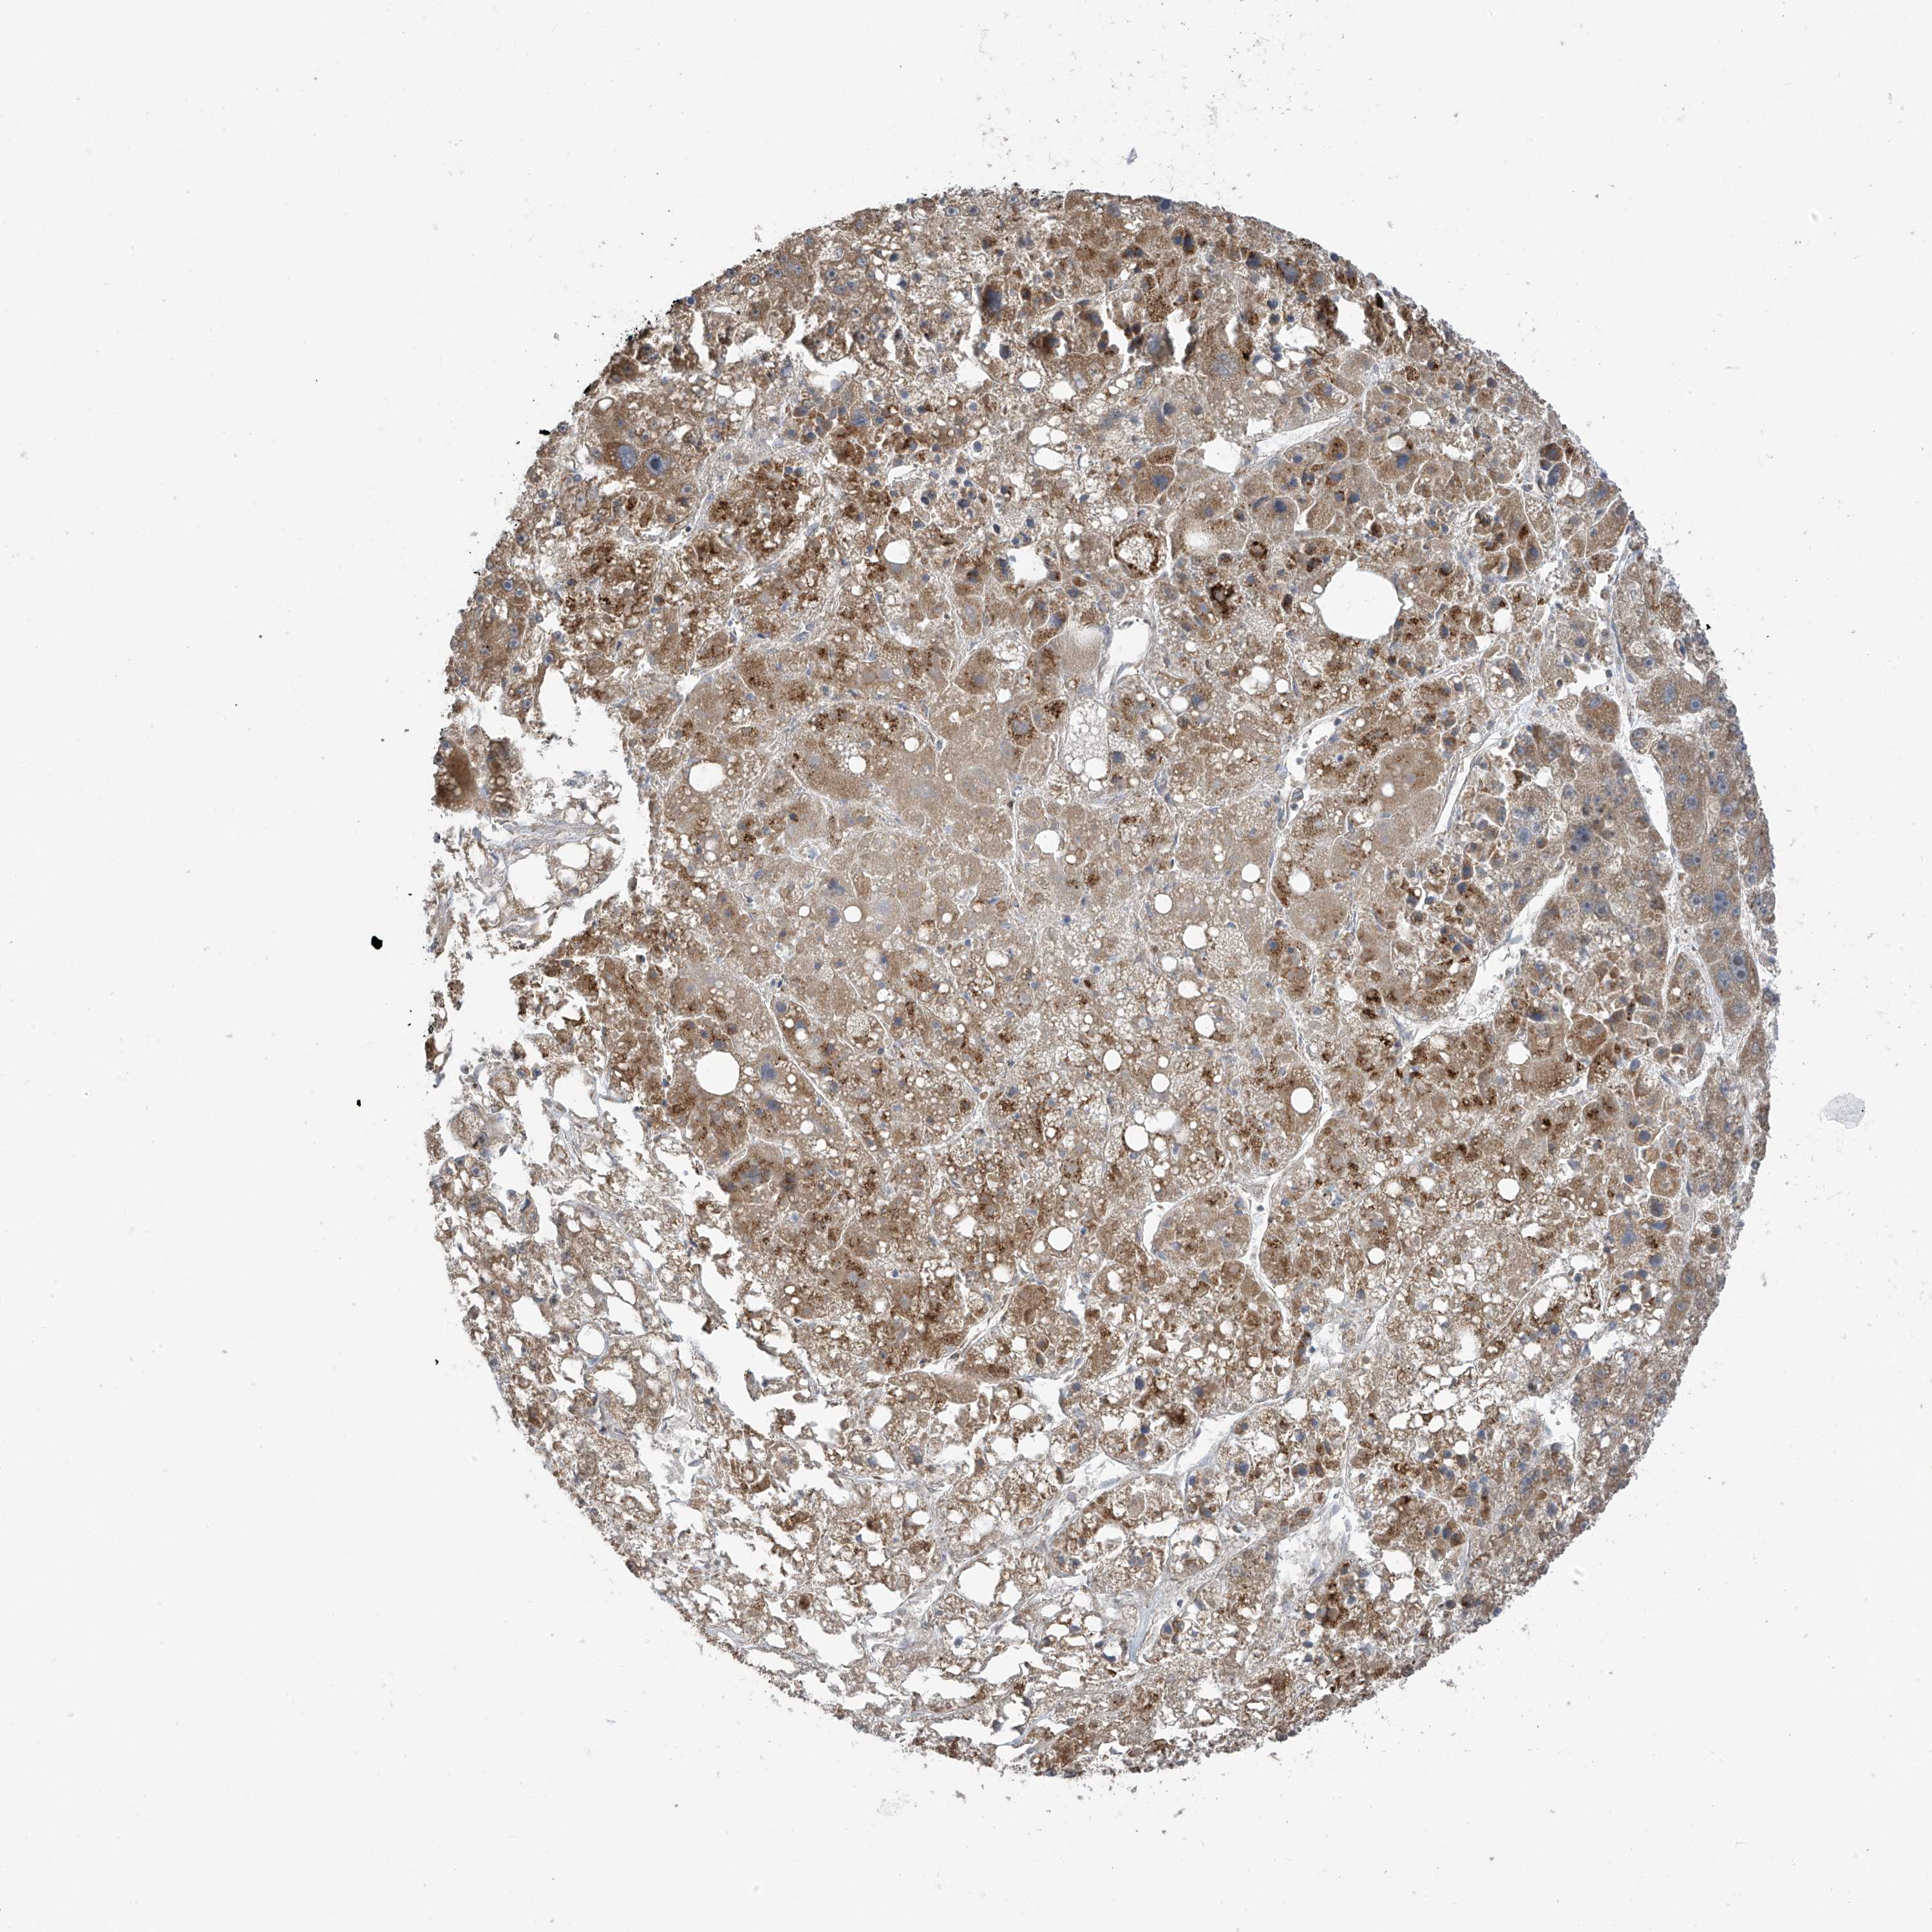

LIVER CANCER - Protein expressioni

A mouse-over function shows sample information and annotation data. Click on an image to view it in a full screen mode. Samples can be filtered based on level of antibody staining by selecting one or several of the following categories: high, medium, low and not detected. The assay and annotation is described here.

Note that samples used for immunohistochemistry by the Human Protein Atlas do not correspond to samples in the TCGA dataset.

Antibody stainingi

Antibody staining in the annotated cell types in the current human tissue is reported as not detected, low, medium, or high, based on conventional immunohistochemistry profiling in selected tissues. This score is based on the combination of the staining intensity and fraction of stained cells.

Each image is clickable and will lead to virtual microscopy that enables deeper exploration of all samples and also displays staining intensity scores, fraction scores and subcellular localization as well as patient and tissue information for each sample.

Antibody HPA034602

Antibody HPA034603

Antibody CAB033424

Staining

High

Medium

Low

Not detected

Intensity

Strong

Moderate

Weak

Negative

Quantity

>75%

75%-25%

<25%

None

Location

Nuclear

Cytoplasmic/membranous

Cytoplasmic/membranous,nuclear

Cholangiocarcinoma

Carcinoma, Hepatocellular, NOS